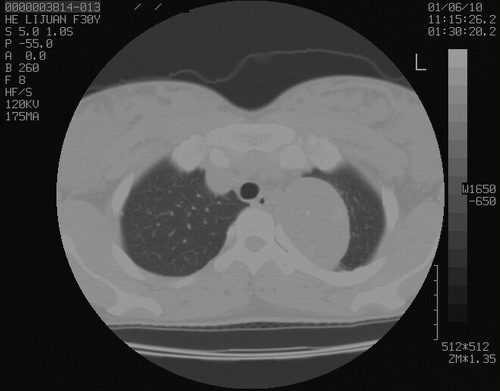

怀孕3个月时(2009-3至4月间),自述突感左侧前后胸疼痛1天,以前胸明显,随后偶感闷痛,余未见异

左肺尖脊柱旁沟肿块,境界清楚,边缘光滑,密度不均,内有多发点片状钙化,考虑良性肿瘤,骨软骨瘤或神经源性肿瘤可能,肺错构瘤不除外。

左后上纵隔见一类圆形肿块影,外侧边界清,密度不均匀,内可见点状钙化影,增强呈不均匀强化,考虑神经源性肿瘤可能。期待病理结果。